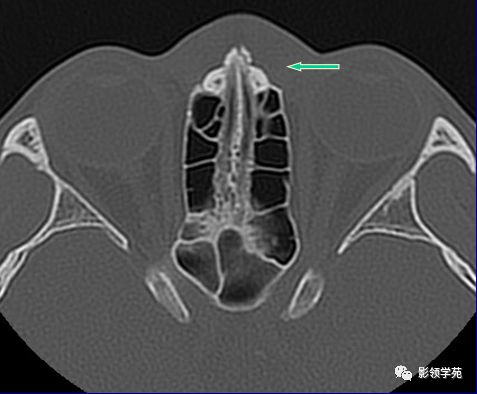

左侧鼻骨线形骨折

右侧鼻骨骨折

左上颌骨额突骨折